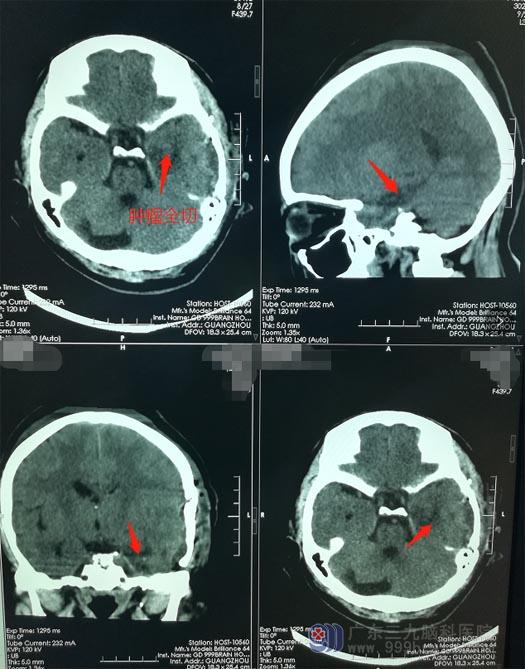

由医院副院长、神经外五科鲁明主刀,行颞部直切口从颞下-天幕入路,该入路可以避免对面听神经的损伤,并且具有操作简单、距离短、广阔的可视化视野等优点,特别是对天幕中切际脑膜瘤,能够减少脑牵拉、术后并发症少、减轻对潜在神经、静脉损伤等优点。术中抬起颞叶寻找肿瘤, 对Labbe 静脉、神经功能保护良好,术中切除部分前颞叶异常放电区。术后未出现后遗症,病理报告:脑膜瘤(Ⅰ级)。